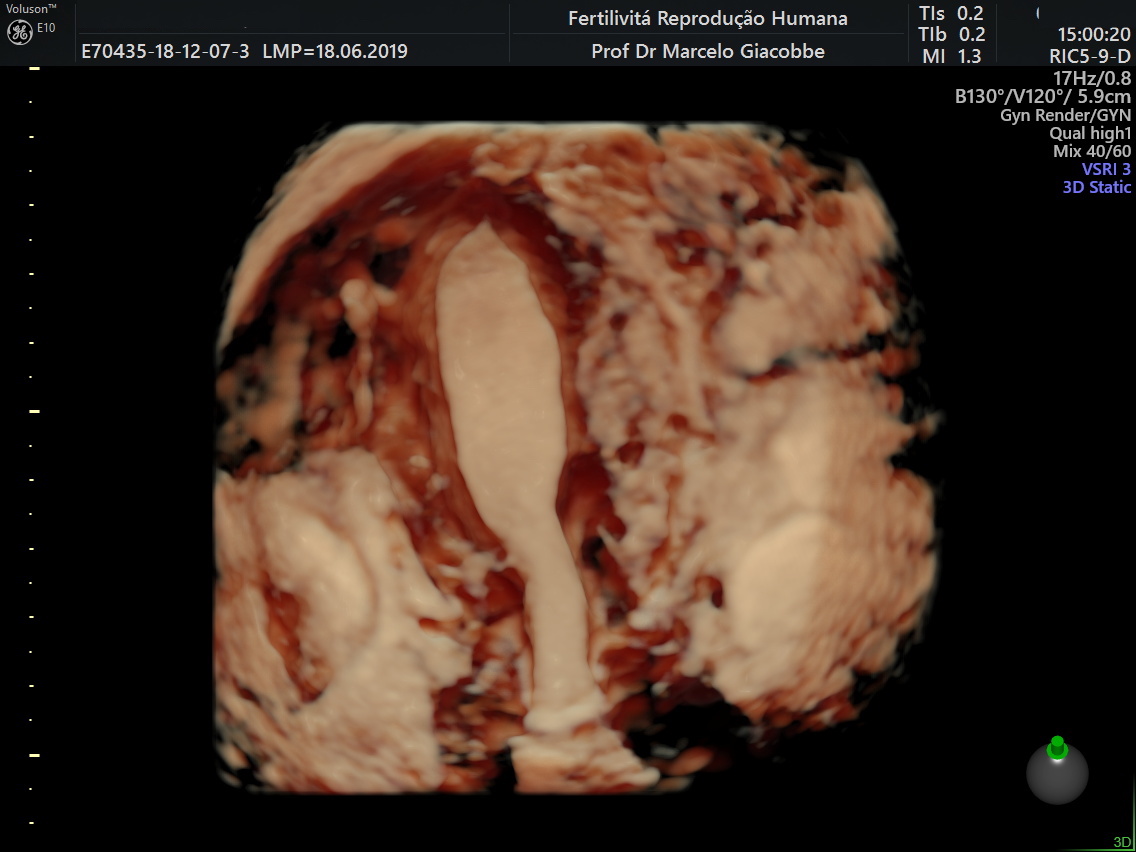

Imagem de ultrassom mostrando hidrossalpinge